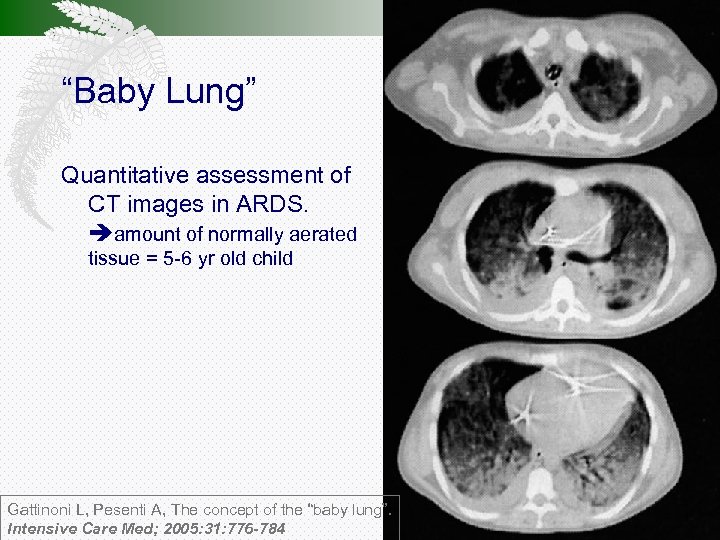

“Baby Lung” Quantitative assessment of CT images in ARDS. amount of normally aerated tissue = 5 -6 yr old child Gattinoni L, Pesenti A, The concept of the “baby lung”. Intensive Care Med; 2005: 31: 776 -784

“Baby Lung” Respiratory compliance correlates with amount of normally aerated tissue Gattinoni L, Pesenti A, Baglioni S et al. Inflammatory pulmonary edema and positive end-expiratory pressure: correlations between imaging and physiologic studies. 1988; J Thorac Imaging 3: 59– 64